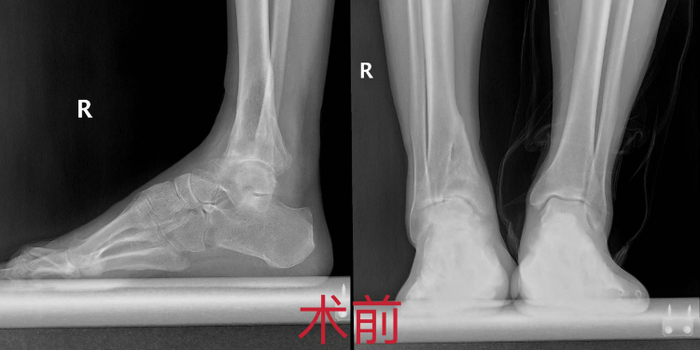

经过细致的查体及相关检查,程相俊副主任医师发现李先生有严重的左踝关节病,关节面破坏严重,不仅存在踝关节内翻畸形,整个后足也存在高弓内翻畸形。同时,通过仔细追溯病史得知,李先生是以前崴脚时把韧带撕裂了,但没有经过规范的保守治疗,才导致病情进展,此时再进行韧带修复或关节松解,已经不能改善疼痛。由于关节软骨受到毁损,如果不进行手术,则会严重影响行走功能。

麻醉、消毒、暴露术区、反复透视、安置假体、后足矫形……历时3小时,程相俊副主任医师团队为李先生成功实施了该手术。做踝关节置换手术需要全面考量,既要考虑临近关节的退变情况,又要考虑踝关节本身的稳定性,李先生不仅存在上述问题,还存在后足的高弓内翻畸形,极大增加了手术难度。经验丰富的程相俊副主任医师在术中对李先生的踝关节和后足问题给予了一并处理。术后检查显示,关节假体匹配良好,下肢力线良好,关节稳定性和活动度同时得以重新恢复。两周后,经过康复治疗,李先生下地行走,功能恢复良好。“疼痛消失,走路稳定,完全超出了预期。”出院时李先生露出了满意的笑容。